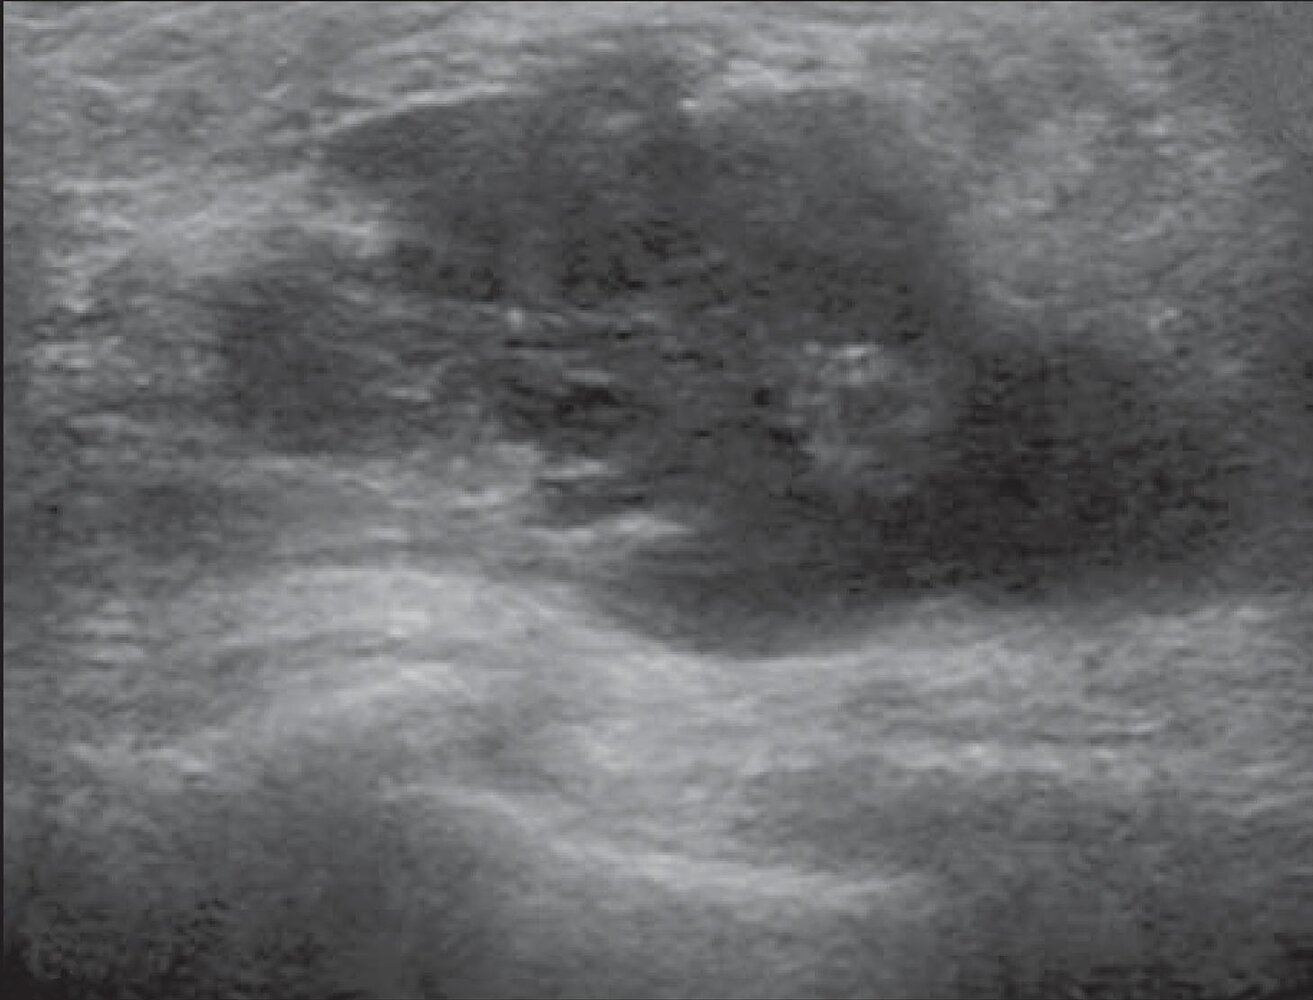

Breast ultrasound [3][4]

• Indications: initial imaging modality for suspected breast abscess [3][5]

• Findings [3][7]

• Irregular, hypoechoic fluid-filled lesions with an echogenic rim and posterior acoustic enhancement

• No vascularity within the fluid collection on Doppler.

• Inflammatory axillary lymphadenopathy may be present.